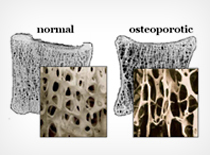

Osteoporosis

Osteoporosis is the thinning of bone tissue and loss of bone density over time.